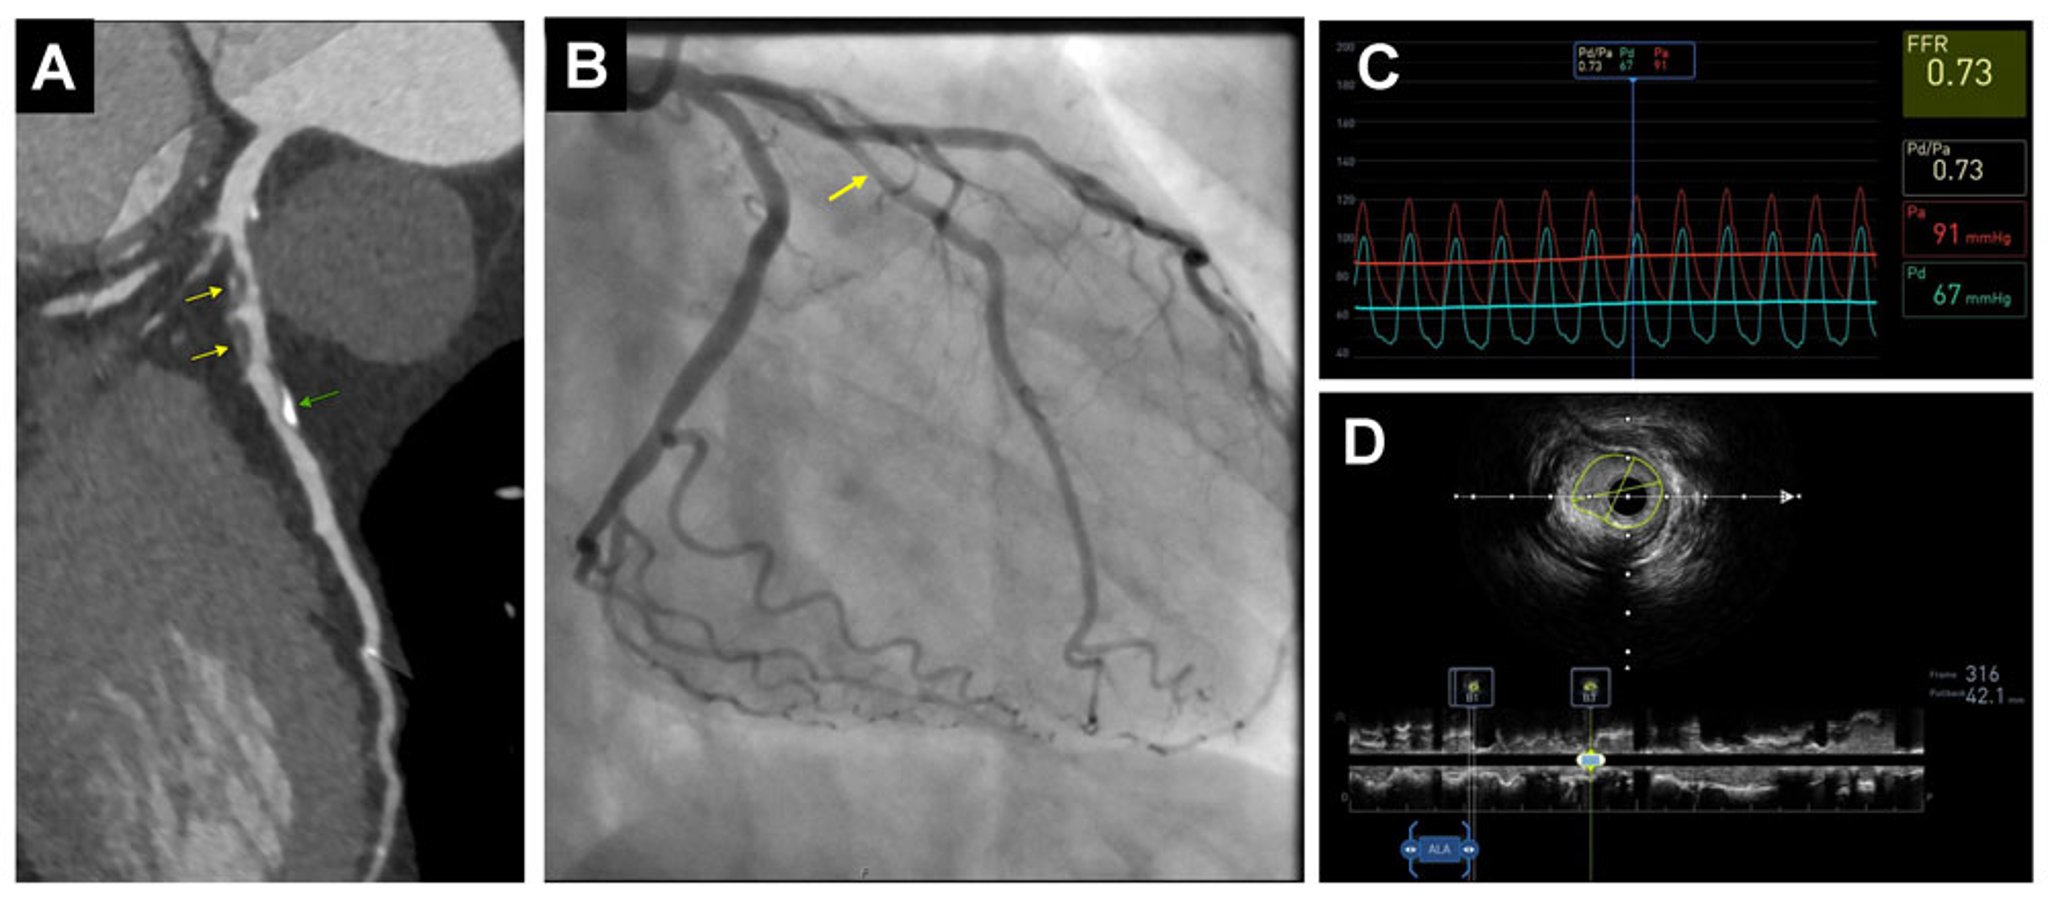

A (left): Coronary CT angiogram shows extensive mixed plaques, both calcified (green arrow) and predominantly noncalcified (yellow arrows)..

B (center): Invasive coronary angiogram confirms moderate left anterior descending luminal narrowing (arrow), which is hemodynamically significant by fractional flow reserve (FFR) assessment (< 0.80) (C, top right).

D (bottom right): Intravascular ultrasound (IVUS)–guided revascularization. The extent of luminal narrowing is visible in cross-section..

Images courtesy of Attila Feher, MD, PhD.